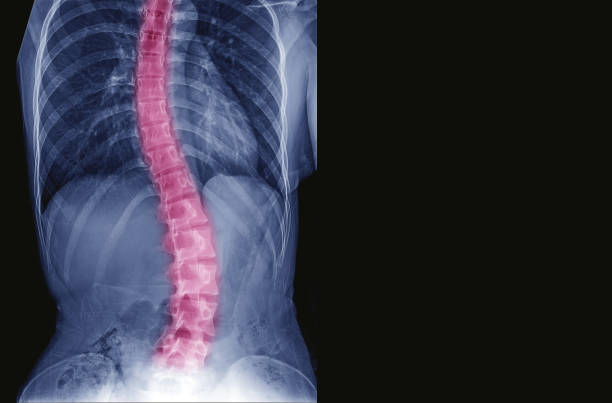

“A Escoliose Idiopática Adolescente (EIA) é uma curvatura anormal da coluna para um dos lados do tronco, trata-se de um desvio de coluna progressivo que pode ou não ser acompanhado de rotação das vértebras. Em 80% dos casos, as causas são desconhecidas e, por isso, ela é descrita como escoliose idiopática”, alerta Dr. Álynson Larocca Kulcheski, médico ortopedista do Hospital VITA, especialista em coluna.

Segundo o ortopedista, é a deformidade mais frequente da coluna. A coluna adquire um desvio das curvas naturais, que pode desencadear um desequilíbrio funcional. O desvio mais frequentemente observado é no plano frontal (visto de frente ou de costas) e nota-se uma inclinação da coluna para um dos lados.

– Desvio da coluna para um dos lados, aparecendo como um “andar torto”, ou “andar inclinado para o lado”, ou mesmo “coluna em S, ou em C”;